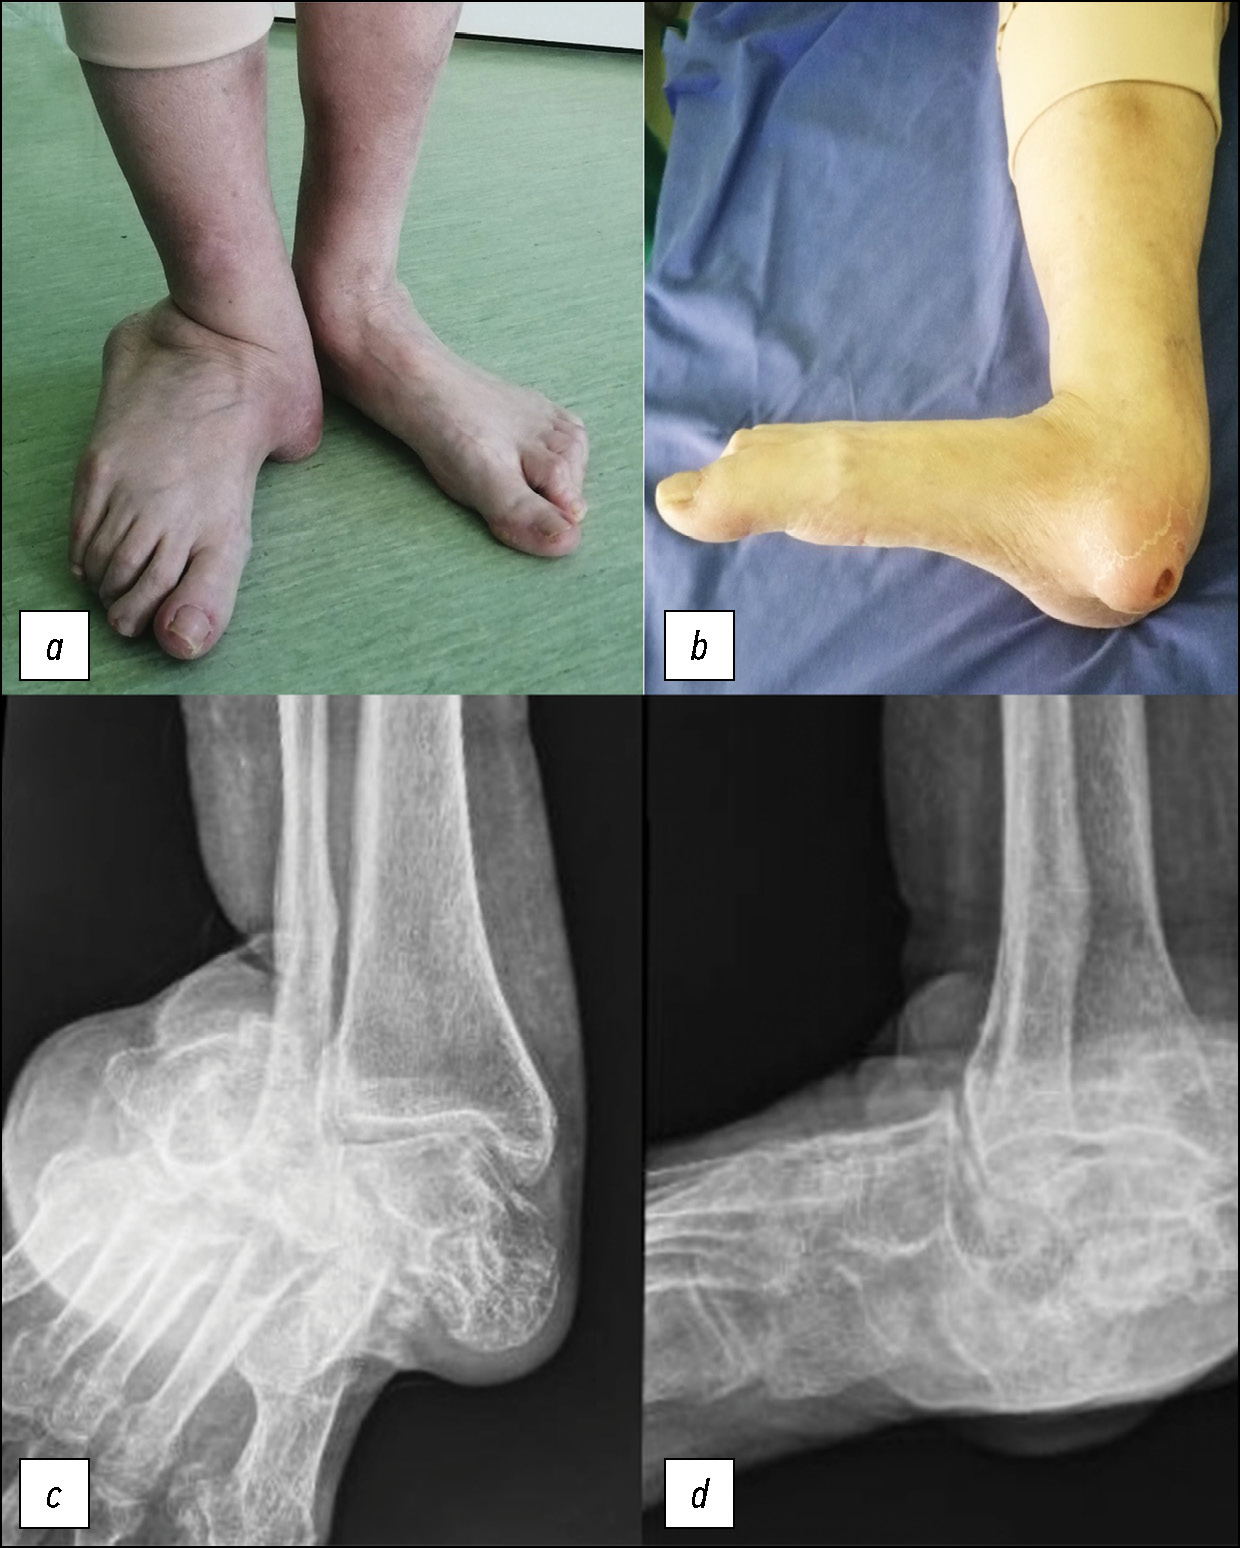

A 55-year-old female patient with rheumatoid arthritis, asthma, and hypertension was referred to the specialist orthopedic clinic by her primary physician due to a 12-month history of progressive right ankle pain and challenges with walking. She denied any history of recent trauma to the affected ankle. Notably, she was diagnosed with acquired flatfoot more than five years ago, which had since deteriorated, resulting in chronic deformity of the left foot and ankle. Upon examination, she exhibited an antalgic gait with signs of discomfort. Although no neurovascular abnormalities were detected, her left foot and ankle demonstrated a pronounced valgus deformity. Notably, the severe valgus deformity caused pronounced skin tension over the medial malleolus, accompanied by skin atrophy and ulceration (Fig. 1). Plain radiographs revealed gross sclerosis and disorganization of foot bones, with medial dislocation of the tarsus, as well as associated lateral dislocation of the calcaneum and cuboid (Fig. 1).

Fig. 1. Clinical image and plain radiography at presentation: anteroposterior (a and c) and lateral (b and d) views.

Рис. 1. Клиническая картина и обзорная рентгенография при поступлении: передне-задний (a и c) и боковой (b и d) вид.